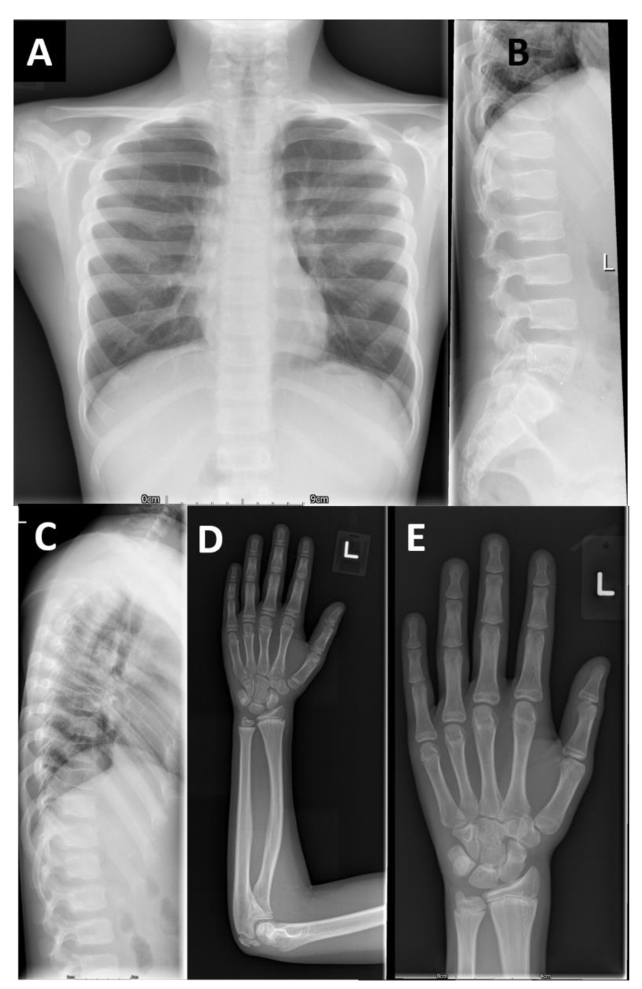

本研究提供了两个家系的详细表型信息,并与两个已发表的病例进行了比较。F2-V-3的放射学发现与之前描述的“先证者1”的放射学发现非常相似,这并不令人惊讶,因为这两个人都有相同的纯合子p.Arg569*。相反,PRKG2家族1有一致的放射学表型,不同于先前报道的AMDP和AMDM。

两个PRKG2变异家族的影像学表现

本文报告的三兄弟 (F1-IV-3、IV-6和IV-7)除了个别F1-IV-7有轻微的脚趾缩短外,没有肢端缩短 (Acromesomelic shortening)的证据。主要发现是颈椎病伴有椎体前突、股骨颈细长、干骺端不规则 (最明显的是桡骨和尺骨)和横纹(Striations)。其中一个儿童的远端指骨干骺端呈圆锥形,但是不显著。综上所述,家族1表现为以脊柱干骺端发育不良 (Spondylometaphyseal dysplasia)为特征的骨骼表型,而不是像AMDP和AMDM所预期的肢端发育不全。

F1- IV- 7的额外影像学表现